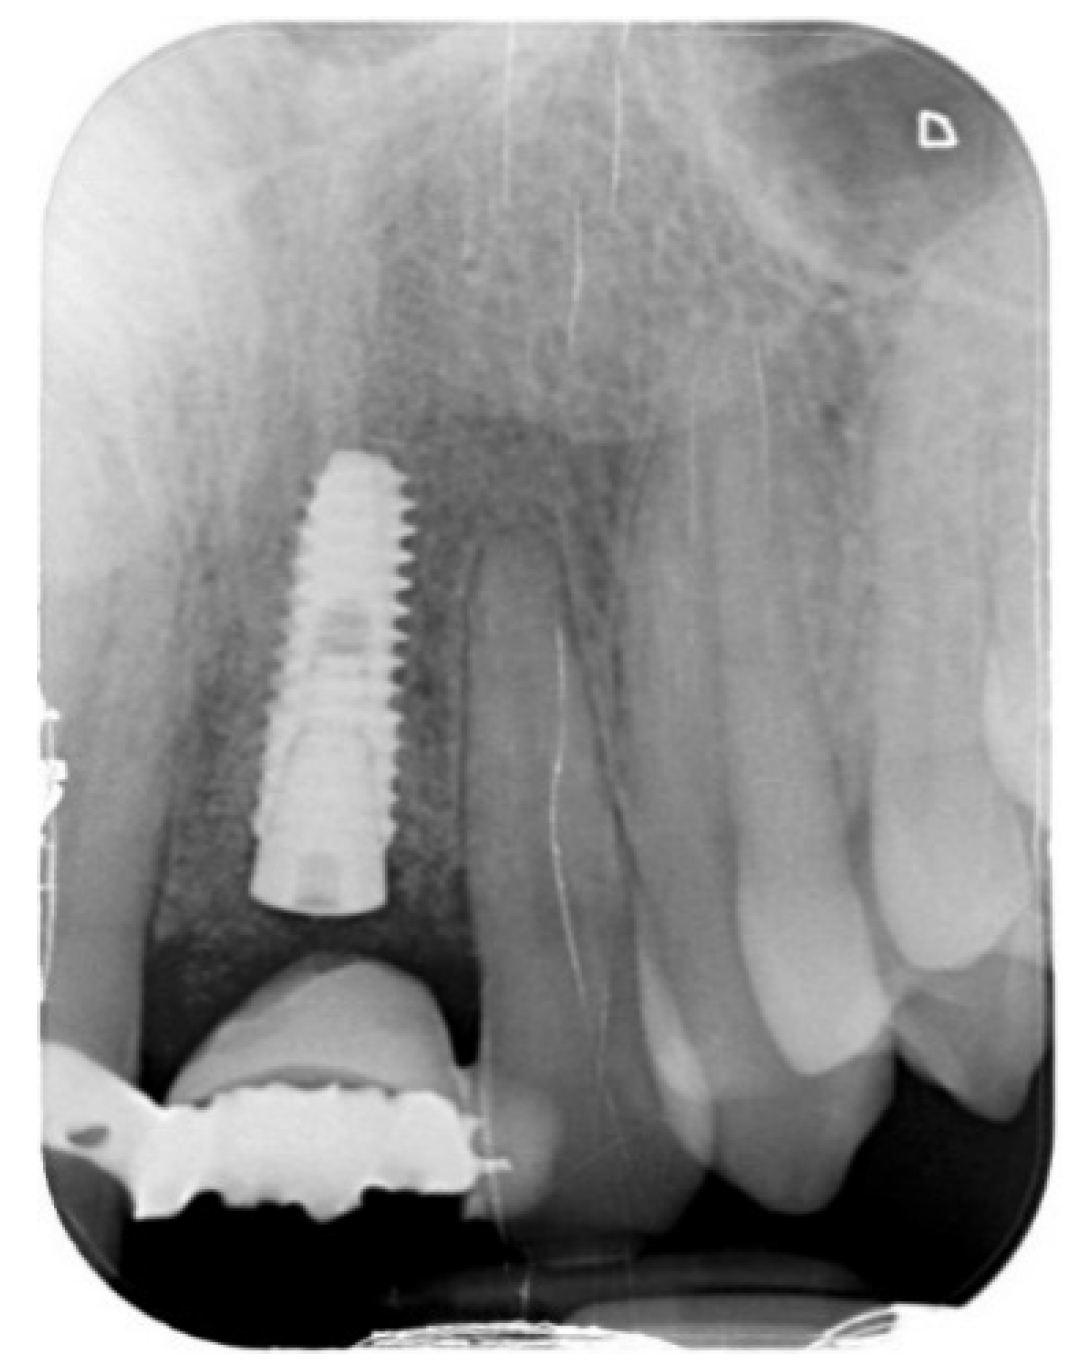

Tissue Recession around a Dental Implant in Anterior Maxilla: How to Manage Soft Tissue When Things Go Wrong?

2. Case Presentation